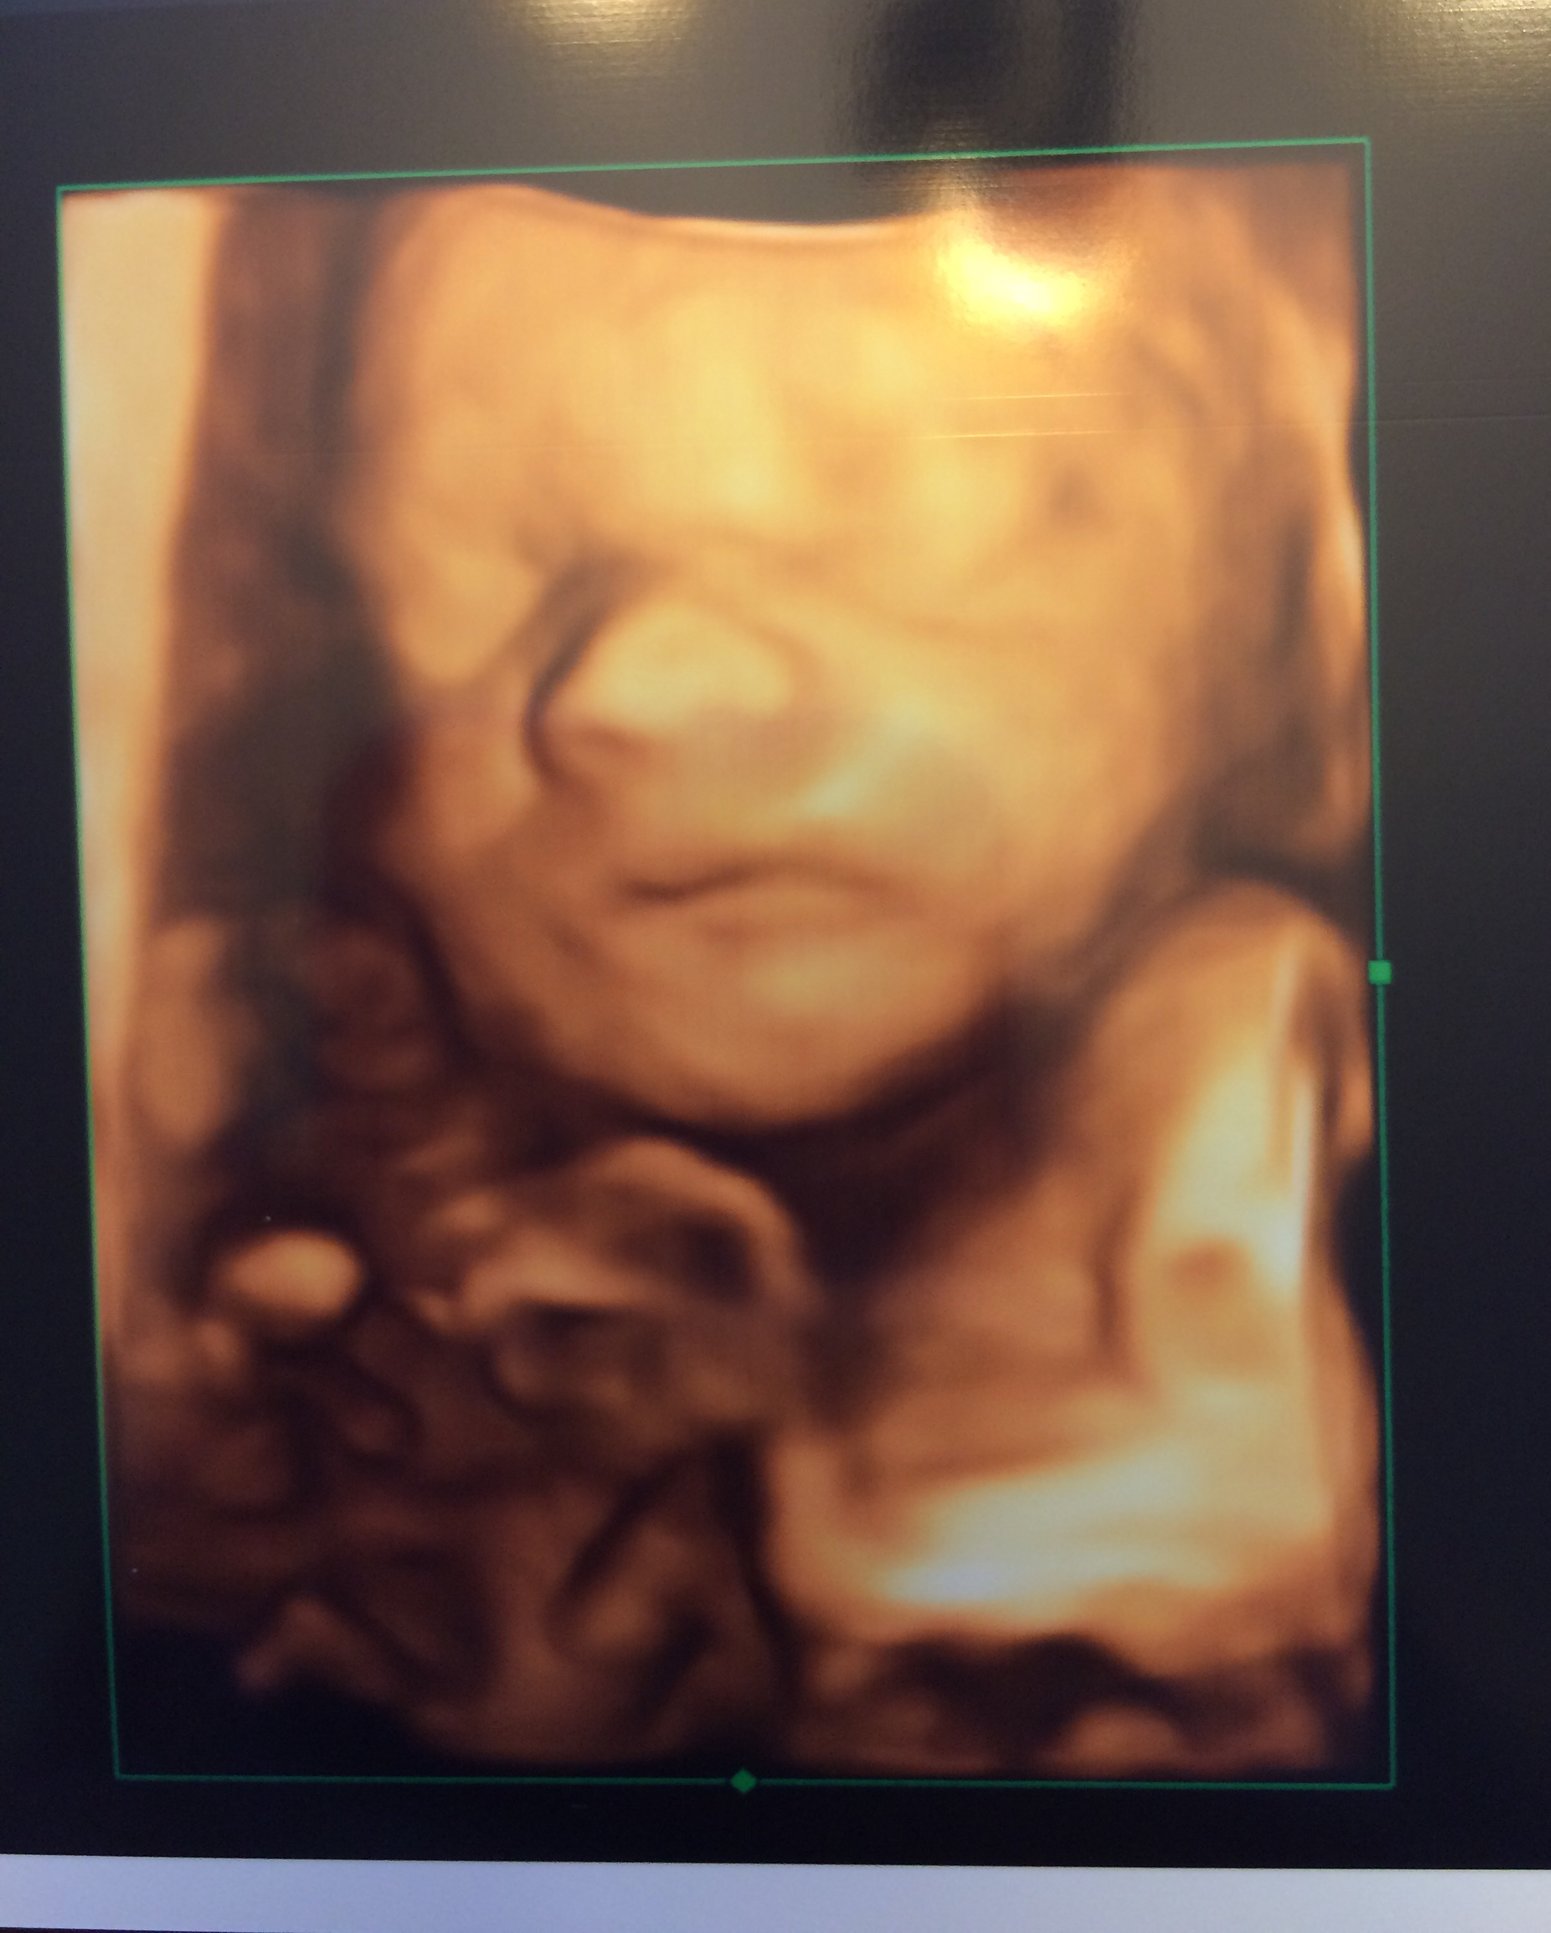

Sorry if giant. 3D ultrasounds are a bit weird but it was so cool to see his face. He has my lips for sure and his daddy's nose. Taken at 25w3d

Our sweet boy taken at 26wks! Due September 10th. Weighing 1.78lb, HR at 140bpm. This is our 1st baby, so we are more than anxious to meet him now that we have a name with a face!